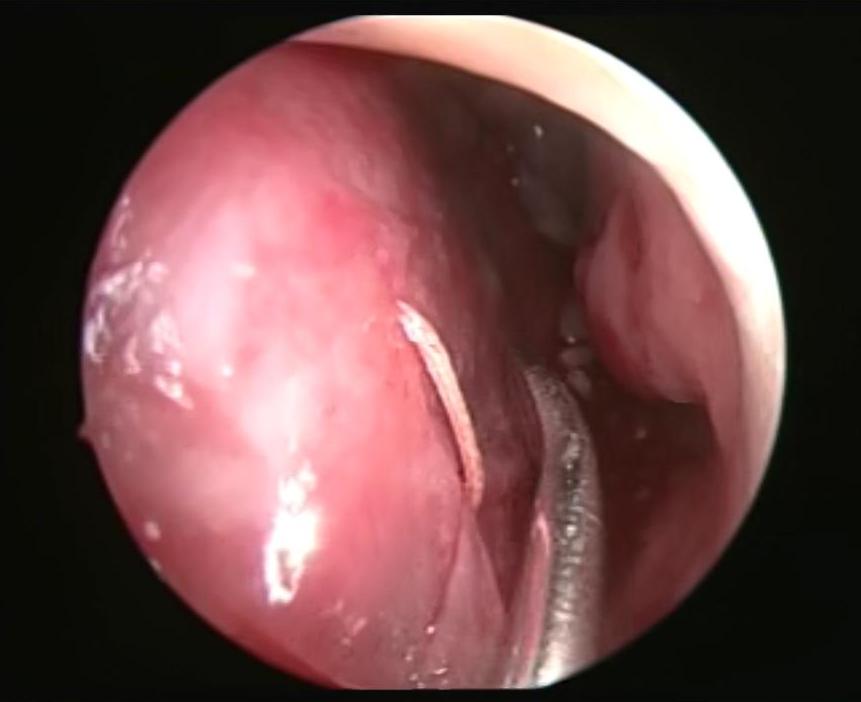

It is an autosomal dominant vascular disorder, which has a variety of clinical manifestations, with epistaxis being one of the most common. Many treatment options exist for epistaxis, but with no consensus on which is the method of choice. We describe the case of a patient with hereditary hemorrhagic telangiectasia (HHT) secondary epistaxis with septoplasty managed with synthetic hard graft, which improved intensity and frequency of bleeding episodes. This technique is a variant of the septodermoplasty described by several authors, but the use of synthetic dura can help in obtaining better results and avoid taking skin grafts from other sites different from the surgical site.